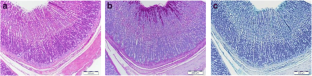

Fig. 1